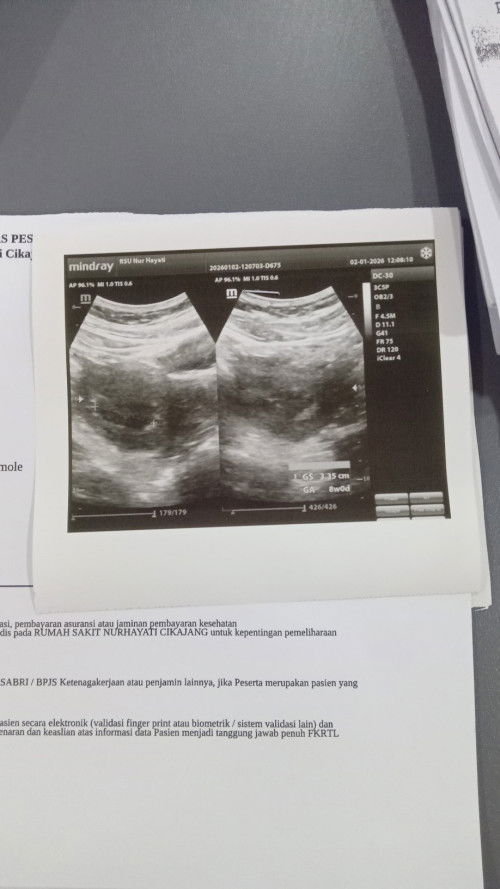

Hallo Bun , saya mau tanya apakah usia kehamilan 8week belum kelihatan jelas kantongnya wajar GK Bun

wajar, kemarin aku juga usg di 7 week 6 d baru kantong juga

kalo aku gaada kak, tapi baru keliatan kantong aja. kakanya minum vit apa?